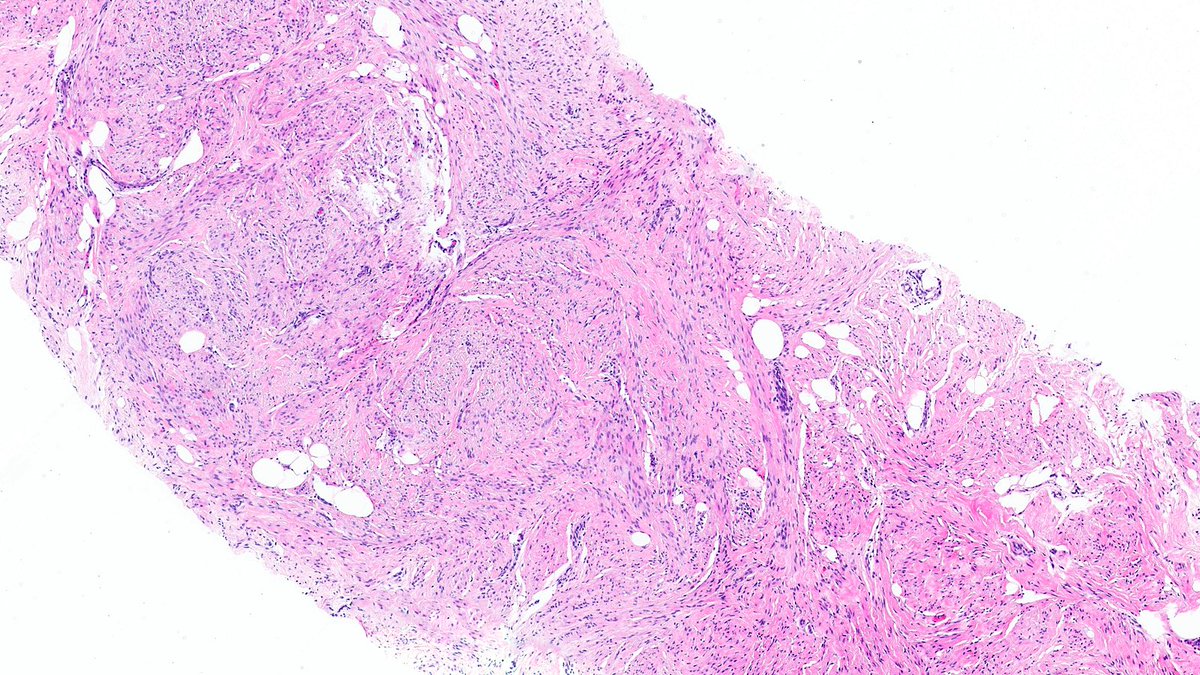

Adult male. Retroperitoneal mass. #PathX #PathTwitter #BSTPath

SumantaDas_7's tweet image. Adult male. Retroperitoneal mass.

#PathX #PathTwitter #BSTPath